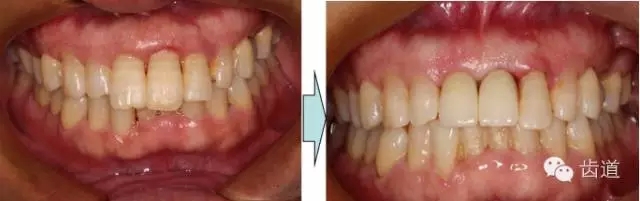

治療前后對(duì)比

本病例為前牙外傷致根折,牙周無(wú)明顯炎癥,唇側(cè)骨板厚度大于1mm且根方骨量充足,適合即刻種植。術(shù)前簡(jiǎn)易導(dǎo)板的制作以及術(shù)中牙周探針精確的測(cè)量,保證了種植體的三維位置及軸向均按標(biāo)準(zhǔn)的即刻種植手術(shù)進(jìn)行。術(shù)后參考拔除牙齒的頸部形態(tài)制作個(gè)性化愈合基臺(tái),實(shí)現(xiàn)了對(duì)牙齦塑型的早期干預(yù),打破了傳統(tǒng)二期牙齦成型的做法,所成型的牙齦袖口與之前的天然牙相似,有利于維持牙齦形態(tài)的穩(wěn)定和美觀。